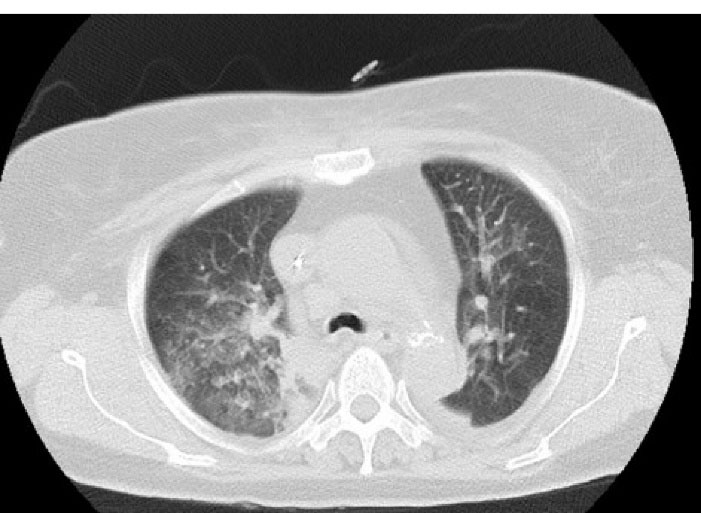

Three hours later, we noticed that she was pale and hypotensive. In physical examination, clear blood was seen inside the patient’s mouth but we did not find any bleeding signs in the nasal-gastric tube. Further, in the chest exam, she had diffuse rales over both lung areas, while there was no hemorrhagic site. Laboratory tests were performed and we found metabolic acidosis and drop of Hb from 13 to 7.5. With abdominal sonography, retroperitoneal hemorrhage was ruled out. Chest radiography exhibited bilateral alveolar infiltrates which was dominant in the right lung. A pulmonary computed tomography scan was done to rule out pneumonia, pulmonary edema, and pulmonary infarct (). With suspected cardiopulmonary edema underwent LAD involvement to roll out of acute mitral regurgitation, repeated echocardiography was done that revealed mild LV dysfunction with mild MR. During the diagnostic evaluations, management steps were started simultaneously, including eptifibatide infusion discontinuation, administration of pack cell, and Fresh Frozen Plasma (FFP). After three days, the patient was extubated but developed a mild right hemiparesis, though brain MRI was normal and ischemic encephalopathy was raised. The patient found worsening hypoxia and alveolar infiltrates were diffused. Six days later based on these clinical manifestations and evaluation results, we suspected the diagnosis of DAH and performed diagnostic bronchoscopy. This revealed distributed dark blood throughout the bronchial tree and displayed on serial bronchiolar lavage hemorrhagic return was increased, thus confirming the diagnosis DAH. shows a chest X-ray eight days later, which alveolar infiltration improved. The patient had hemoptysis for 2 weeks. Also, she had functional loss in daily living activity. For rehabilitation and function improvement, she was transferred to the subacute geriatric ward. One month later, the patient was discharged with a relatively good general condition. Now, after 4 years, the patient is symptom free and on re-catheterization all the stents were patent.

Figure 2.

Areas of consolidation, ground-glass, and normal in pulmonary computed topography scan.